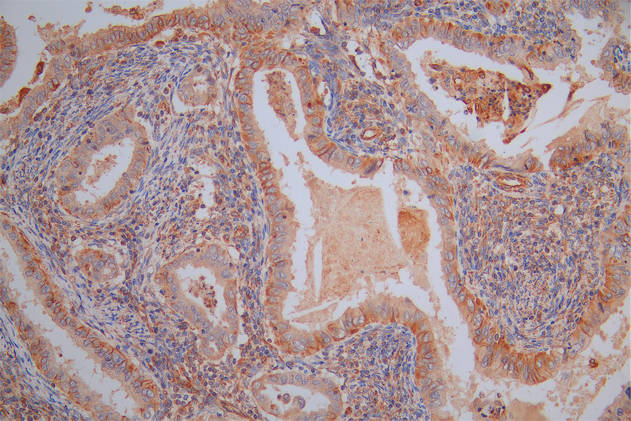

Immunohistochemistry of paraffin-embedded human small intestine tissue using CSB-PA619964LA01HU at dilution of 1:100